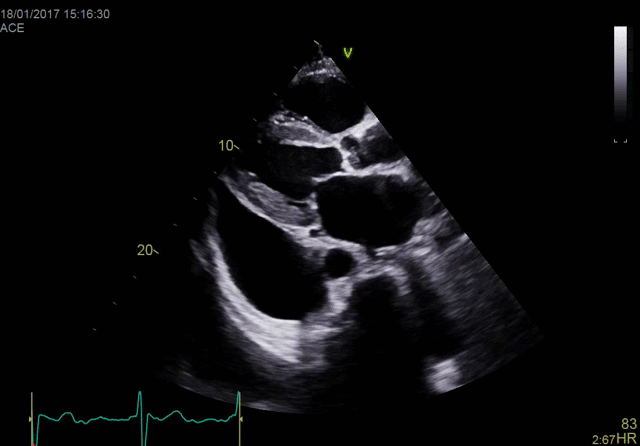

Объединяя проверенную мощность и производительность линейки Vivid с мощной программной платформой формирования ультразвукового луча cSound для реконструкции изображений, система Vivid E90 переносит ультразвуковую диагностику на совершенно новый уровень, помогая минимизировать неинформативные исследования и снизить стоимость услуг.

В сравнении с многими традиционными аппаратами УЗД эта система позволяет получать больше данных, используя технологии точной конфокальной визуализации (TCI) и адаптивного контрастного усиления (ACE) для получения изображений высочайшего качества. Кроме этого система оснащена многими высокоточными инструментами количественного анализа и функциями, оптимизирующими рабочий процесс.

- Детализированное отображение структур сердца для улучшения взаимодействия между врачами УЗД и интервенционными кардиологами (хирургами).

- Улучшенные характеристики:

- качества изображений в ближней зоне обзора;

- четкости отображения латеральных стенок;

- однородности изображений;

- проникновения.